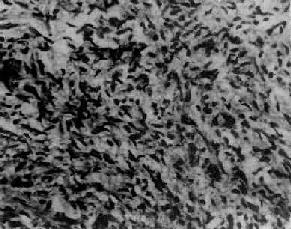

图13-20 粒层细胞

细胞排列成小卵泡型,部分细胞核呈现核沟

肉眼观,肿呈圆形、卵圆形或分叶状,大小不等,多数小于15cm,表面光滑,常有完整的包膜。切面多为实性,质地稍硬,肿呈黄白色,有些可呈囊性变,常有坏死出血区。多为单侧性。镜下,细胞多呈小圆形或多角形,胞浆少。核圆、椭圆或梭形,核膜清楚,核内常可见纵沟,核染色质细,可见1~2个核仁,核分裂像较少见。组织学类型有以下几种:分化较好的细胞常排列成小卵泡型(图13-20),呈菊形团或小腺泡状,中央为粉染蛋白液或退化的细胞核,称Call-Exner小体;有的排列呈大卵泡型、梁柱型或岛状等;分化较差的细胞常排列呈弥漫型或波纹状、脑回状或肉样构型。